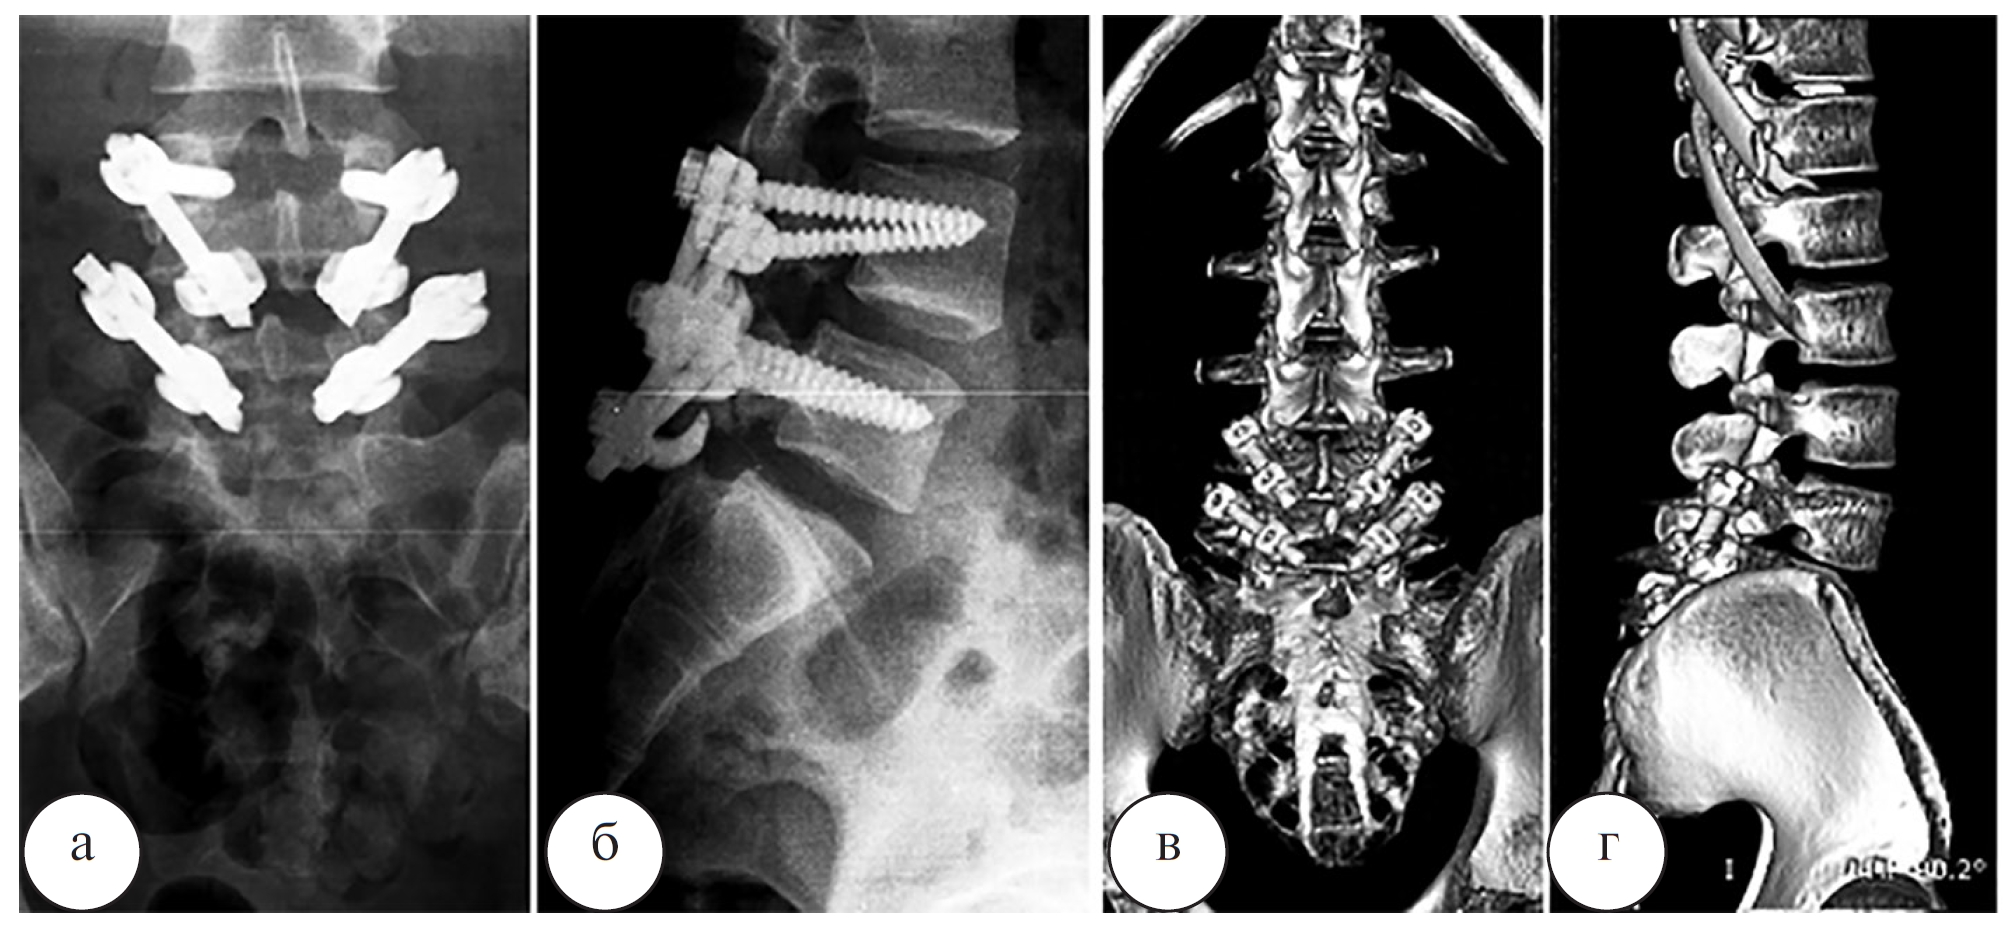

Наблюдение 2. Пациент Л., 19 лет, рядовой контрактной службы. По данным спондилографии, КТ и МРТ позвоночника (рис. 5, 6) был выявлен двусторонний спондилолиз L4, L5 позвонков, минимальный спондилолистез L4 позвонка (I степени). Выполнена операция: костная аутопластика, задний спондилодез дужек четвертого и пятого поясничных позвонков ламинарно-транспедикулярной системой (рис. 7).

Рис. 7. Рентгенограммы пояснично-крестцового отдела позвоночника (а – переднезадняя проекция; б – боковая проекция) и 3D-компьютерные томограммы пояснично-крестцового отдела позвоночника (в – переднезадняя проекция; г – боковая проекция) пациента Л. после операции

Длительность операции составила 200 мин, кровопотеря – 200 мл. При контрольных осмотрах было отмечено снижение интенсивности болевого синдрома в соответствии с визуальной аналоговой шкалой боли (visual analog scale – VAS) с 9 до 2, а также значений индекса Освестри (oswestry disability index – ODI) – с 65 до 10%. Начальные признаки сращения спондилолизных дефектов в зоне костной пластики по данным КТ были выявлены уже через 3 месяца после операции (рис. 8).

Ранних и поздних осложнений после операций не было. Во всех случаях достигнута стабильная компрессия и фиксация спондилолизного дефекта с двух сторон. У двух пациентов со спондилолистезом I степени по данным контрольной спондилографии была отмечена частичная или полная редукция смещенного позвонка (табл.). Длительность операции при одноуровневом спондилолизе составила в среднем 154±25 мин, кровопотеря – 100–150 мл. В целом результаты лечения больных прослежены в сроки от 1 года до 8 лет после операции. Отчетливые признаки перестройки костных трансплантатов в зоне спондилолизных дефектов были выявлены при контрольной КТ через 4–6 месяцев после операции. Полное сращение спондилолизных дефектов в зоне костной пластики было отмечено через 8–12 месяцев. Все пациенты отметили купирование болевого вертеброгенного синдрома в течение первого месяца после операции. Во всех наблюдениях прогрессирования спондилолистеза отмечено не было. После периода реабилитации все пациенты вернулись к прежнему уровню физической активности, а через 12 мес. после операции средние значения индекса ODI снизились до уровня минимальных нарушений. В течение периода наблюдения прогрессирования дегенеративного процесса в смежных межпозвонковых дисках не отмечено.